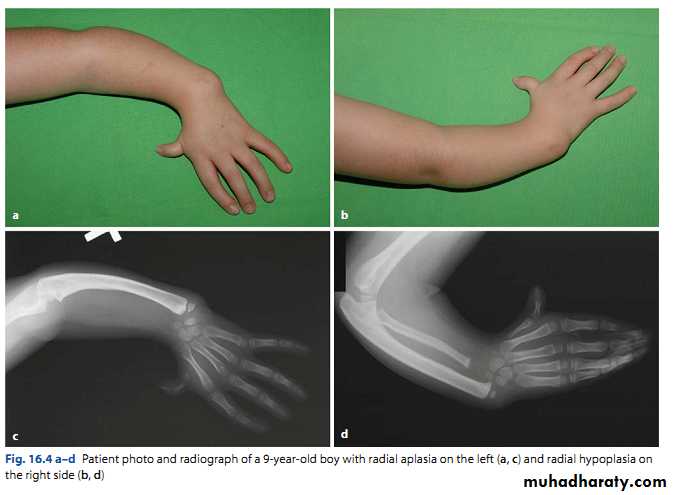

Radial club hand

Partial or complete absence of the radius with radial deviation of the hand.

May be associated with other congenital anomalies or blood dyscrasias (eg thrombocytopenia).

Treated by serial manipulation and casting then surgical correction.